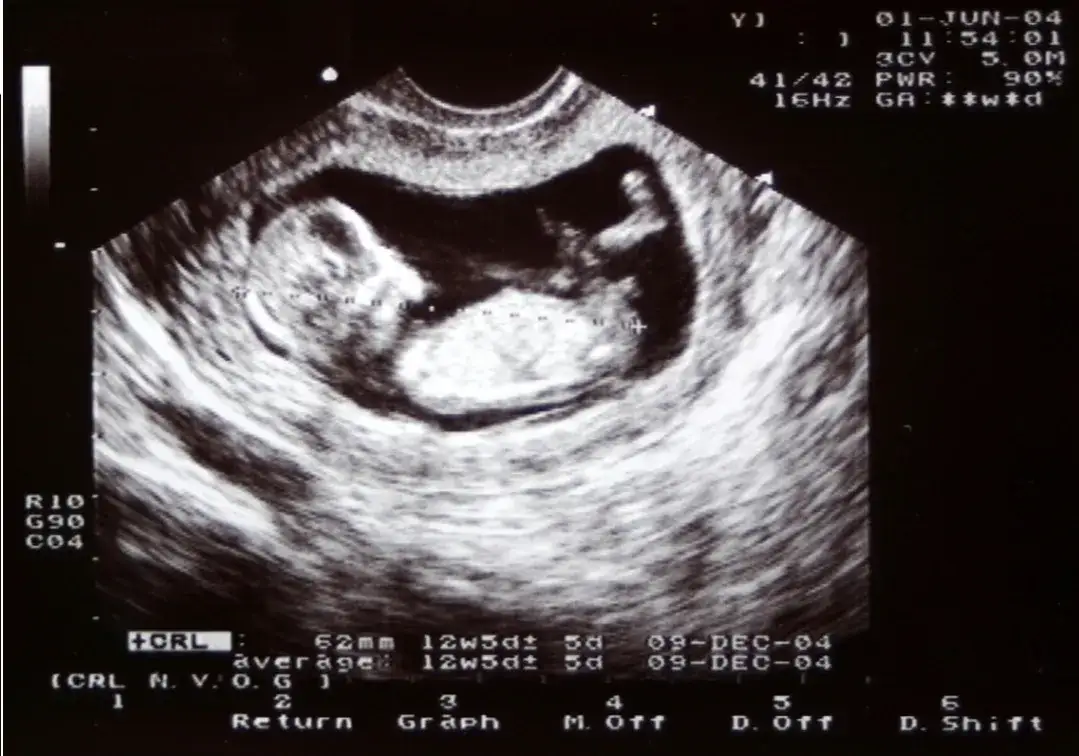

Rozpoznanie ruchów dziecka w brzuchu może być wyzwaniem, zwłaszcza dla kobiet, które doświadczają ciąży po raz pierwszy. Ruchy te zazwyczaj zaczynają się pojawiać między 12. a 20. tygodniem ciąży, ale ich intensywność i charakter mogą się różnić. Na początku są to często delikatne odczucia, które mogą przypominać pękające bąbelki powietrza lub lekkie łaskotanie. W miarę jak dziecko rośnie, te ruchy stają się bardziej zdecydowane i łatwiejsze do zidentyfikowania.

Natomiast ruchy dziecka, które zaczynają być odczuwane zazwyczaj między 16. a 20. tygodniem ciąży, są bardziej wyraźne i zdecydowane. Kobiety opisują je jako kopnięcia, uderzenia lub salta, które są regularne i mają swoje unikalne rytmy. Ruchy te są zazwyczaj bardziej intensywne i mogą być odczuwane w różnych miejscach brzucha, w zależności od pozycji dziecka. Warto zwrócić uwagę na te różnice, aby lepiej zrozumieć, co dzieje się w organizmie w czasie ciąży.